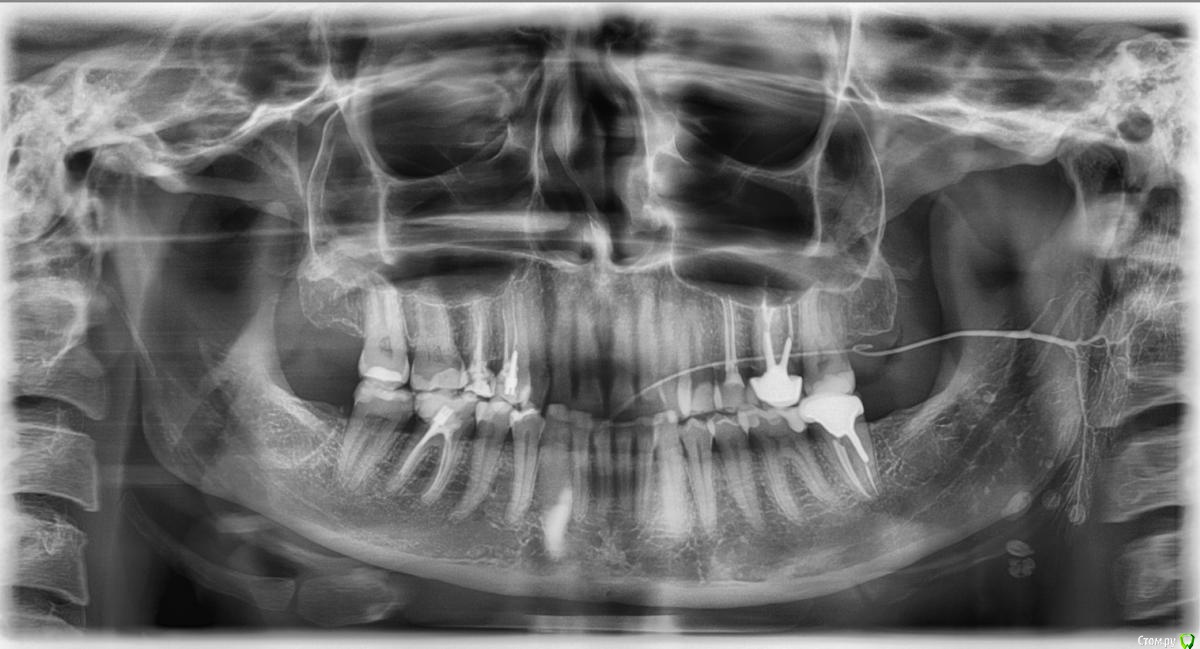

Прошу помочь с установлением причин увеличения лимфатических узлов. В начале мае произошло онемение челюсти после сна с левой стороны. За 6 часов мне удалось разработать челюсть и чувствительность вернулась. Однако так продолжалось 4 дня. Я обратилась к стоматологу за помощью. В ходе осмотра была обнаружена небольшая дырочка на 36 зубе. При вскрытии зуба врач предположила пульпит, но в связи с тем, что отсутствовала реакция на холодное и горячее, а также боль при постукивании, приняла решение лечить как обычный кариес. По окончанию лечения предупредила о том, что как появится острая боль следует обратиться за профессиональной помощью. В июне месяце у меня увеличились подчелюстные лимфатические узлы, позднее распространились на шею слева. Периодически наблюдается температура субфебрильных значений. Проехала ни один челюстно-лицевой институт, никто ничего не нашел.

В начале сентября появилась острая пульсирующая боль в 36 зубе. Обратилась в стоматологическую клинику. Во время обработки каналов были обнаружены изменения, который ближе к 37 зубу. Врач положила лекарство на 2 недели. Лимфатические узлы уменьшились, температуры не наблюдалось. Через 2 недели поставили постоянную пломбу и все вернулось, а может даже и увеличились ещё больше. По словам врача, каналы в порядке. Наблюдается боль в процессе чистки зубов и при употреблении твердой пищи. С момента установки постоянной пломбы прошло 1,5 недели. Температура 37,1-37,5.

Прилагаю снимки с сиалографии до лечения и рентген после. Надеюсь на вашу помощь.

Сделайте 3д томограмму есть подозрения на процесс в 3.7 зубе, и точно по датам распишите что когда лечилось и какие были симптомы.